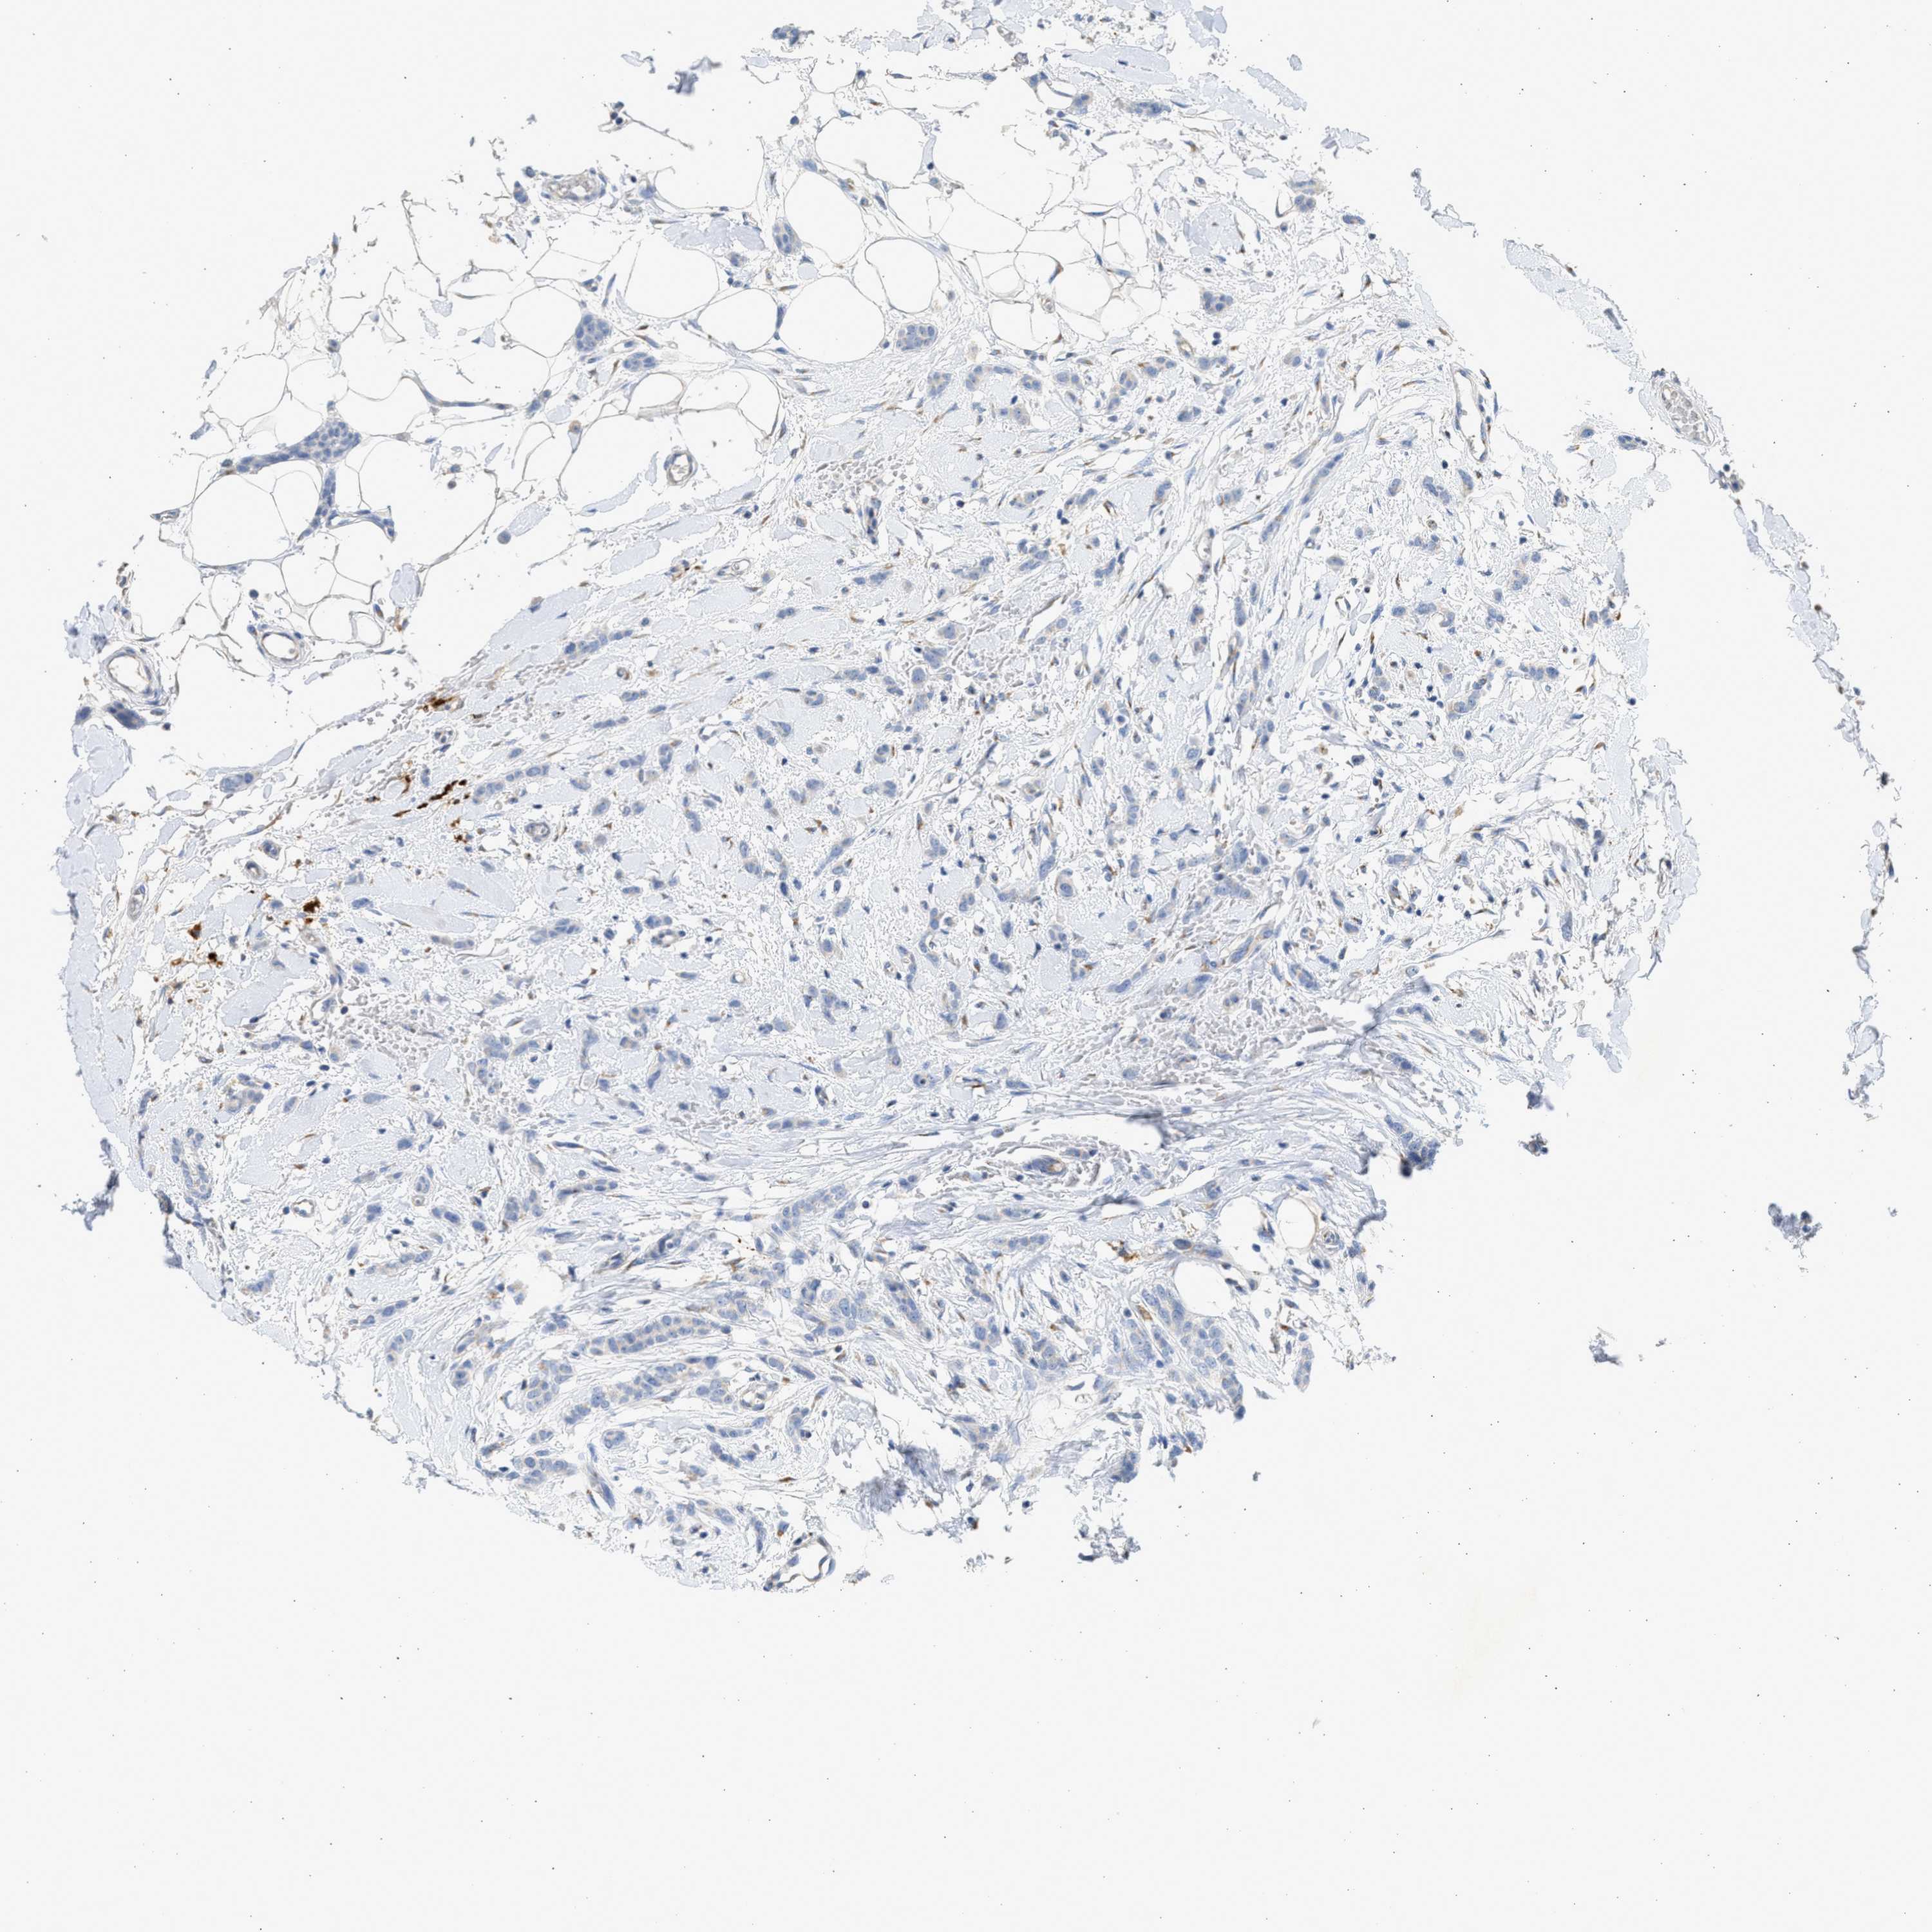

CANCER BREAST CANCER Show tissue menu

BRCA TCGA BRCA VALIDATION PROTEIN EXPRESSION